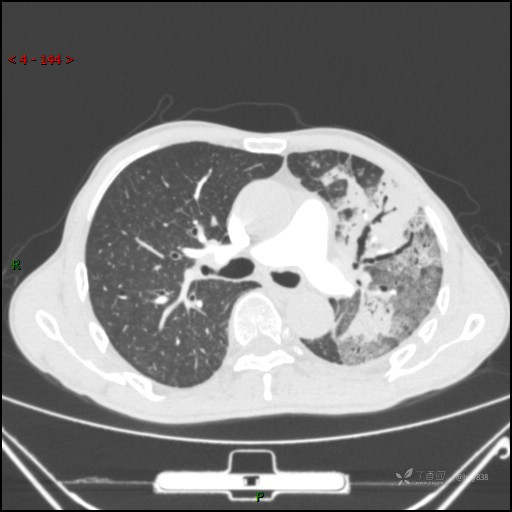

四天后复查(怀疑肺栓)